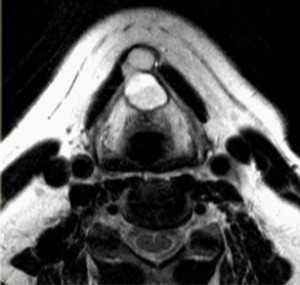

(Слева) КТ с КУ, аксиальная проекция. Образование овальной формы в заднемедиальном отделе сонного пространства. Обратите внимание, что сонная артерия находится на передней поверхности опухоли, а внутренняя яремная вена - на латеральной. Незначительное накопление контраста не очень характерно для шванном, в данном случае вид опухоли напоминает нейрофиброму.

(Справа) MPT Т2ВИ, аксиальная проекция. Округлое образование с неоднородным сигналом, которое смещает общую сонную артерию кпереди. Внутренняя яремная вена смещена вместе с артерией. При сдавливании яремной вены ее идентификация может быть затруднена.